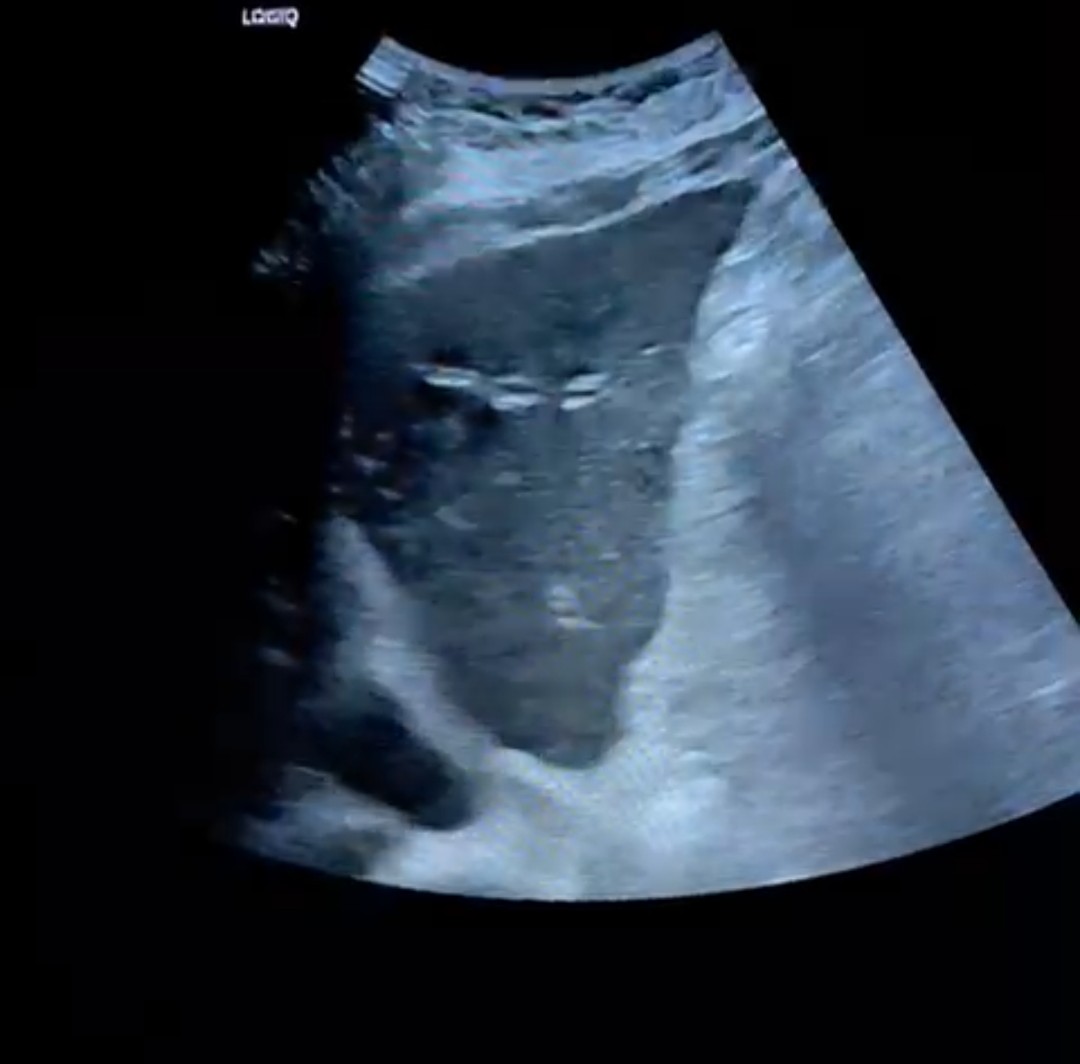

La paciente acude tras una semana de tratamiento antibiótico con cultivo de orina negativo. Persiste febrícula y molestias en hipocondrio derecho. Realizamos ecografía clínica donde se observa lesiones compatibles con metástasis. Se decide ingreso para estudio. Tras TAC de abdomen, TAC de tórax y colonoscopia no se observa tumor primario. Se decide una colangio-RM donde se observa tumoración quística en páncreas con anatomía patológica compatible con adenocarcinoma mucinoso de alto grado en páncreas.

Adenocarcinoma mucinoso de páncreas con metástasis hepáticas.

Es importante el diagnóstico diferencial de la fiebre sin foco, no pudiendo descartar además de los procesos infecciosos, los oncológicos, debiendo preguntar por síntomas constitucionales. En este caso la ecografía clínica abdominal dio con la clave del diagnóstico.